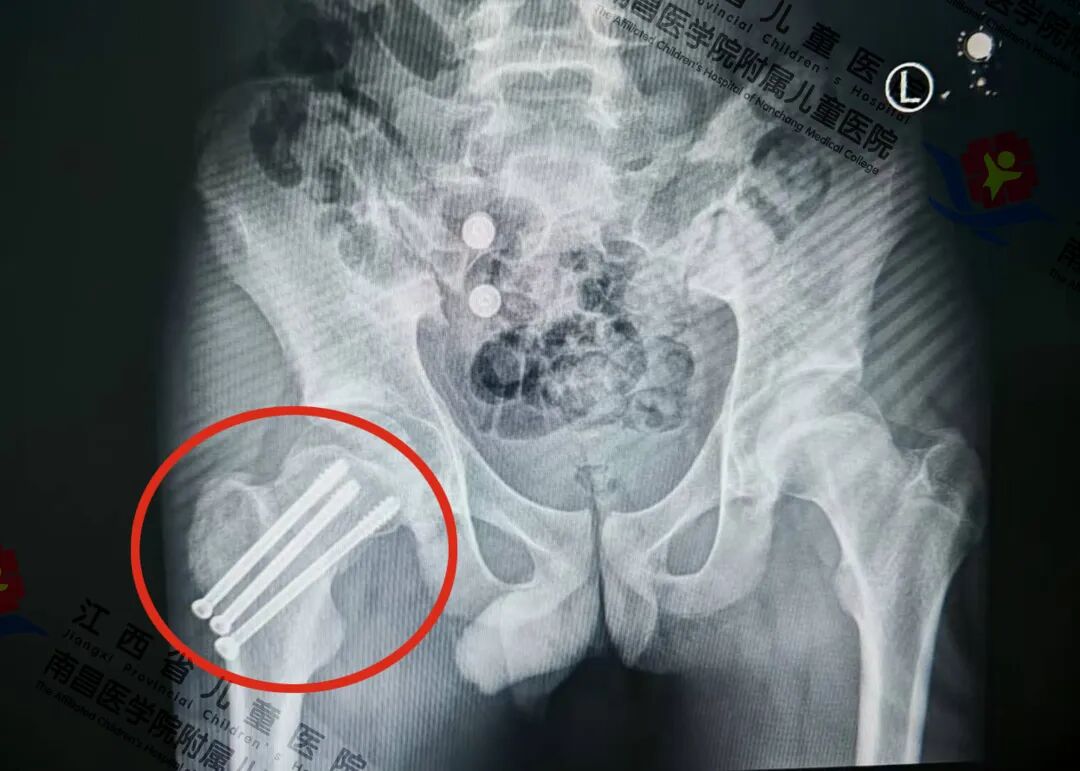

在征得家属同意后,骨科副主任医师熊志刚、邹俊,主治医师熊飞团队为小鸥采用下肢牵引联合手法复位,在C臂机透视下进行精准定位,确认骨折端对位对线满意,随后,彻底引流出髋关节内积血以减轻关节内压力,并用数枚空心拉力螺钉经皮钻入固定骨折端。该术是在不切开骨折断端的前提下,通过肢体牵引和手法复位,将骨折断端对合,实现解剖复位,再用骨钉经皮钻入进行有效内固定。该手术方式为微创术式,有利于骨愈合,减少出现股骨头坏死等并发症率,从而最大限度降低远期残疾风险,为小鸥争取最佳肢体功能恢复。目前,小鸥已出院。

术后